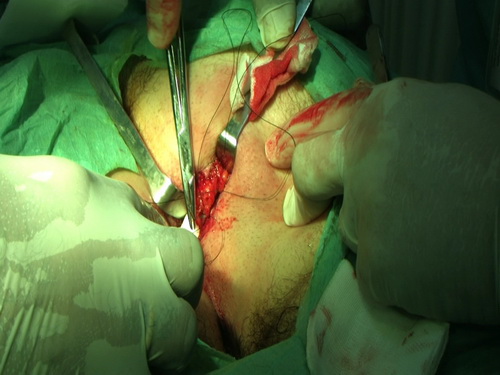

Presenta herida por asta de toro en zona yuxta anal superior izquierda. Cornada peri anal.

Presenta trayectoria única de 18- 20 cm de longitud que no evidencia comunicación con canal anal ni recto y se dirige hacia delante adentrándose en periné anterior.

El orificio externo de la herida presenta colgajo lateral de piel y tejido subcutáneo con evidente desflecamiento de bordes resultantes del estiramiento que sufre la piel por el asta del burel.

ver detalles en el material gráfico que presentamos a la consideración de los compañeros sanitarios.

Se explora concienzudamente la herida. Se eliminan colgajos y detritus, se hace hemostasia cuidadosa, se pone drenaje de Penrrose y se empaca la herida.